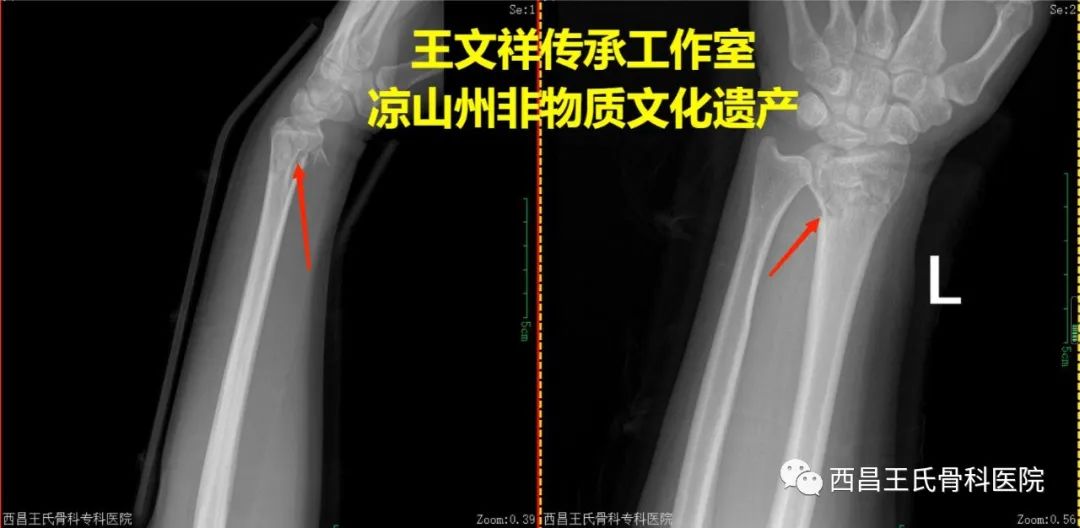

手法复位病例二:桡骨远端粉碎性骨折(院外片)

复位前

复位后